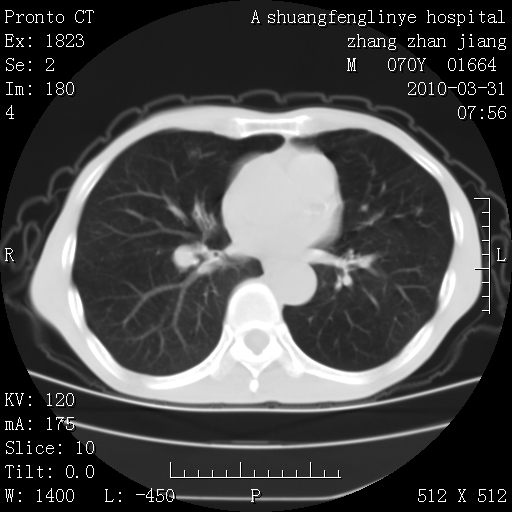

支持,不过左肺中叶那个像陈旧病变的结节要不要单报一下,在图上没看到钙化单报一下放心啊

双上肺继发型tb并左上空洞形成,主动脉冠脉钙化。

1)两肺上叶继发性肺结核并左肺上叶空洞形成。2)冠状动脉及主动脉钙化。